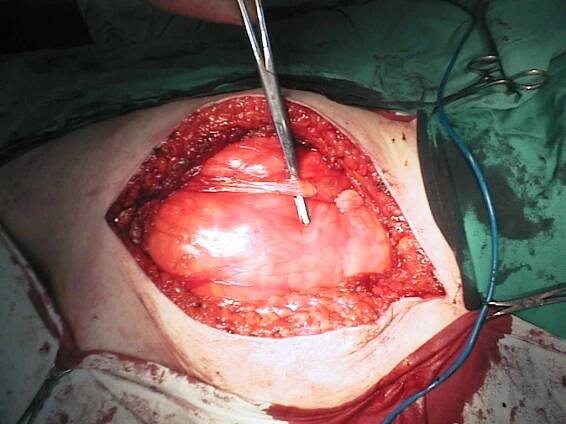

Myoma Large Myomectomy IVF

gynsafe.com